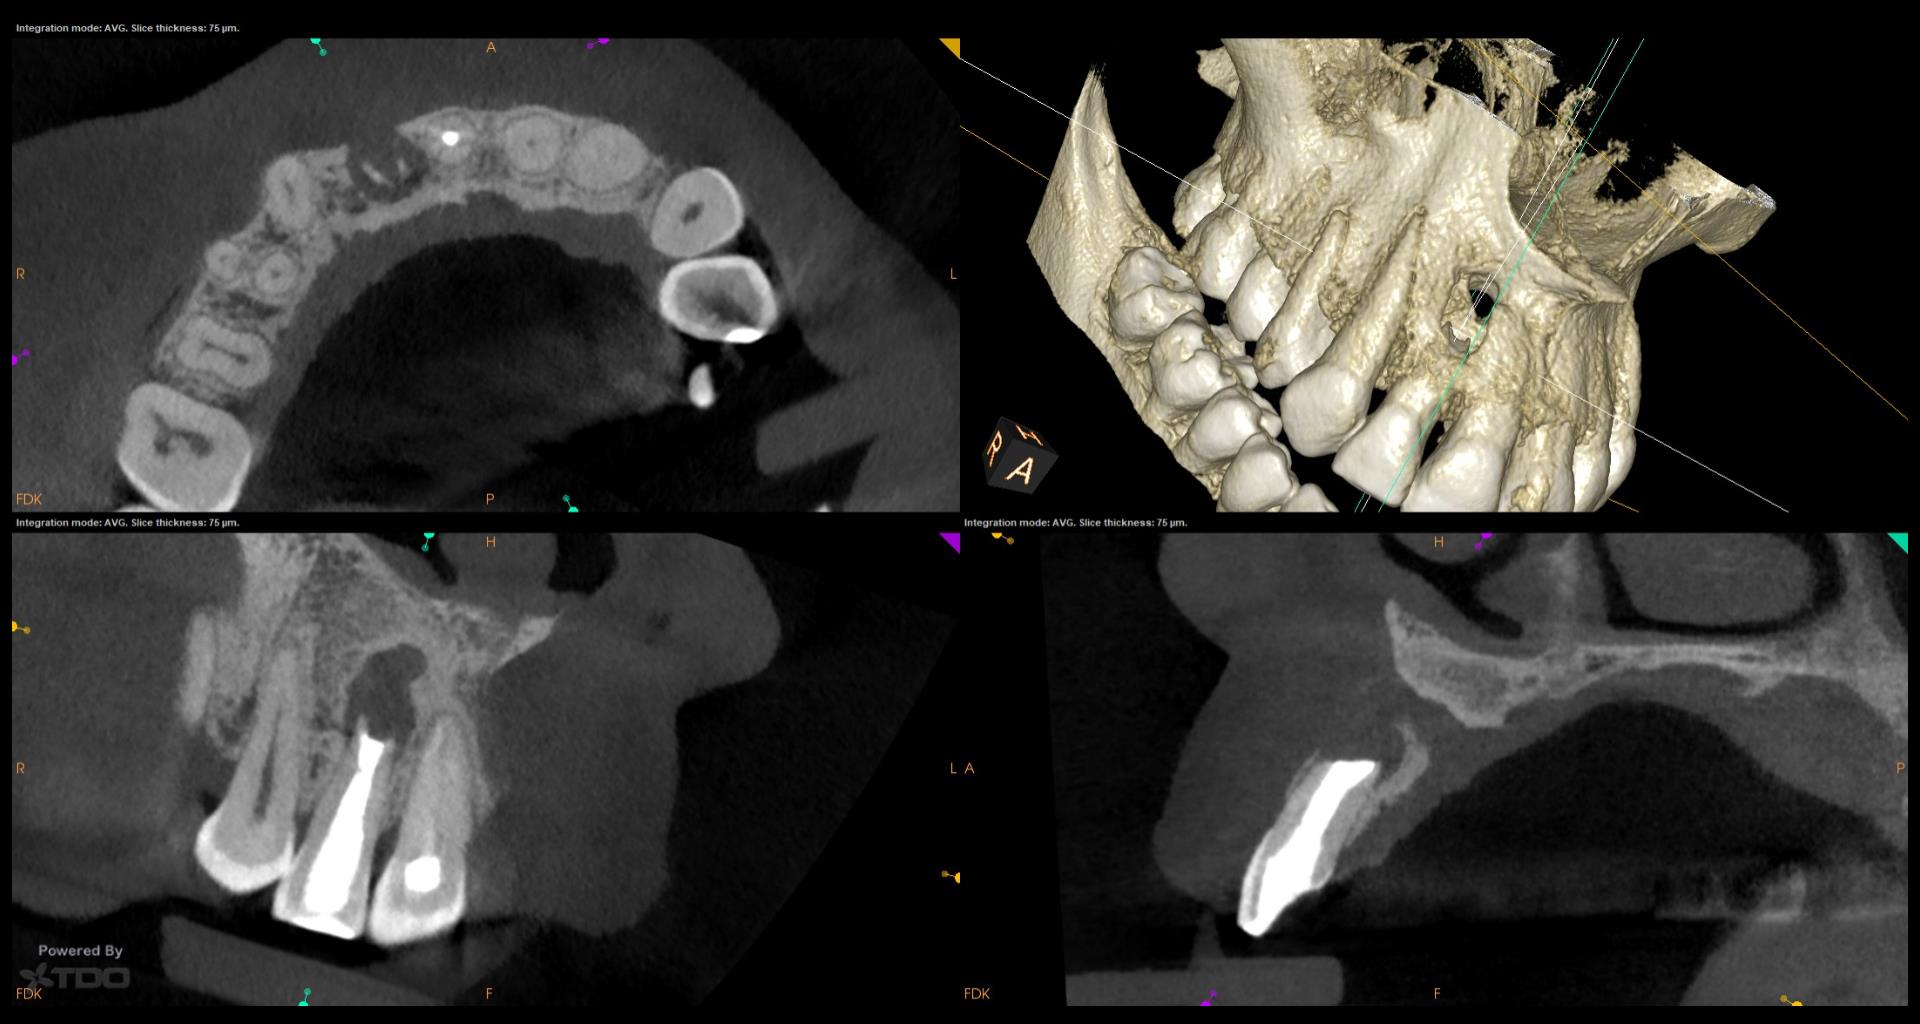

Do you have the previous review x ray s,

Interesting case, Gary. Asymptomatic, but 17-year recalls are crucial! Maybe a bitewing radiograph to check for interproximal caries? A preventative approach avoids future, more involved treatment. Reminds me of needing a winning strategy in Retro Bowl to avoid penalties later on!